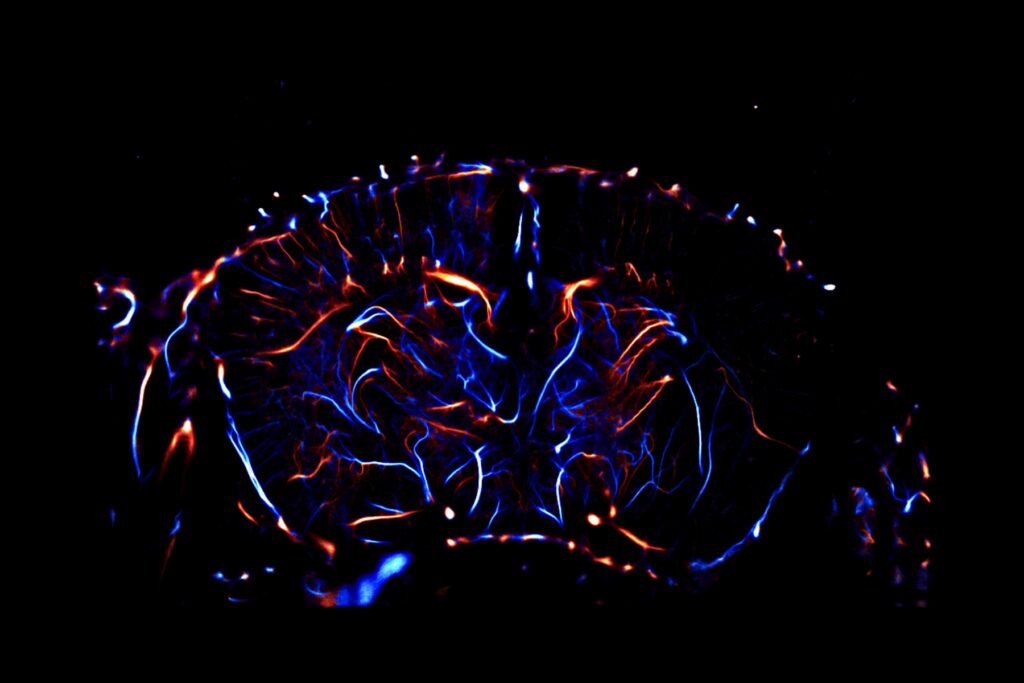

The efficacy of your molecules can be assessed using a set of complementary and multi‑scale approaches: anatomical and molecular medical imaging, neurofunctional imaging, behavioral monitoring, immunohistochemical analyzes, and molecular biology. Every parameter of the study design – administration route, timing, therapeutic regimen, readouts, group size, and inclusion of reference compounds – is customizable and carefully harmonized to meet your specific needs.

Immunohistochemistry, Immunofluorescence, and Histology